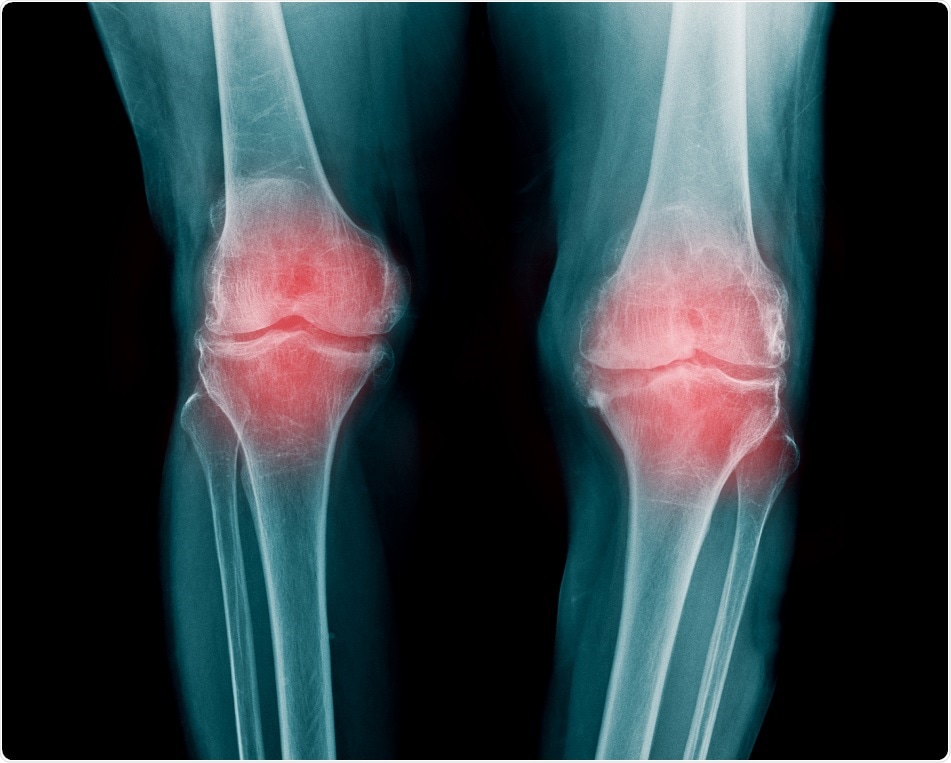

Credit: Tridsanu Thopet/ Shutterstock.com

According to the Centers for Disease Control and Prevention, obesity is considered as a major root cause of osteoarthritis, a chronic joint disease that generally affects adults over 60 years. Osteoarthritis most commonly affects the knee joint, and in many cases, this condition worsens until the total replacement of knee becomes necessary.